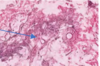

The wall of which cyst?

Periapical Cyst

Open clear areas = Cholesterol clefts where fat

used to be. Multinucleated cells (purple dots)

What is this and what is it associated with?

keratin pearl – can be associated w/SCC